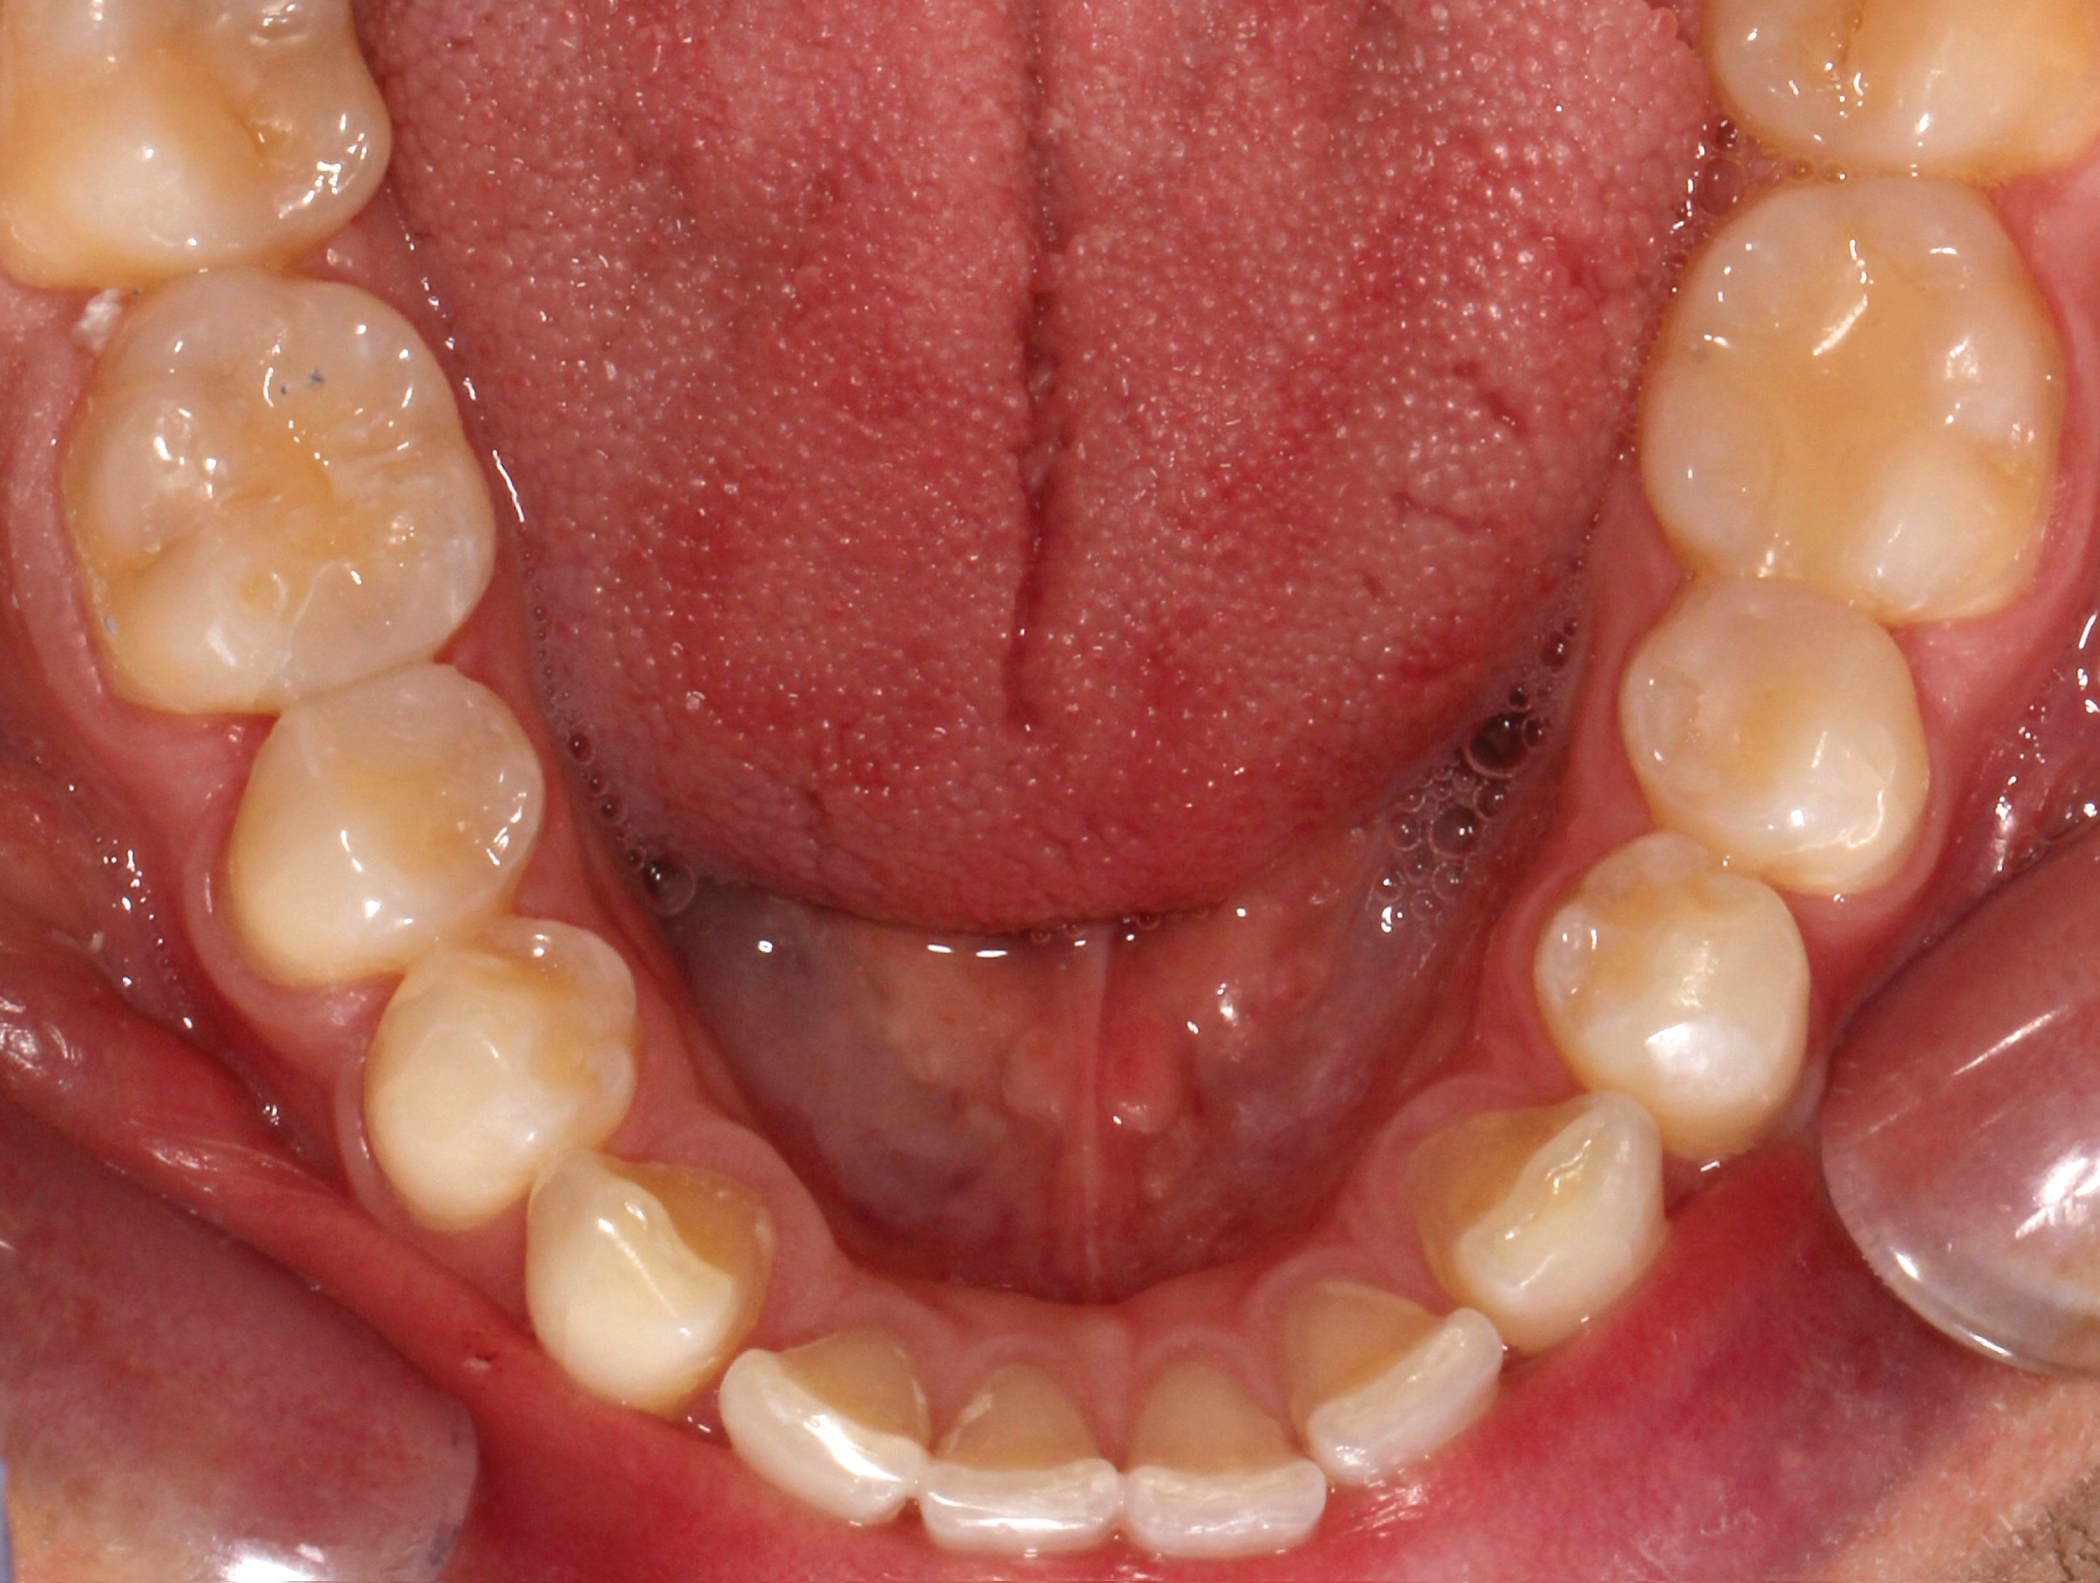

The treatment goals for clear aligner therapy were focused on rotating tooth 9, extruding tooth 9 and subsequent enameloplasty to even out the maxillary anterior teeth. The patient also had mild Class II molar and canine relationships with crowding and spacing discrepancies in the anterior teeth. The goal with the extrusion of tooth 9 was to move the adjacent bone and soft tissue coronal with the tooth movement. Additional space was needed for the maxillary teeth to accommodate the rotation of tooth 9 into the correct position. Lastly, extra spacing between the lower teeth was to be treated along with the mild Class II malocclusion (Figs. 1-8).

Fig. 5: Pre-op (upper occlusal view) Fig. 6: Pre-op (lower occlusal view)